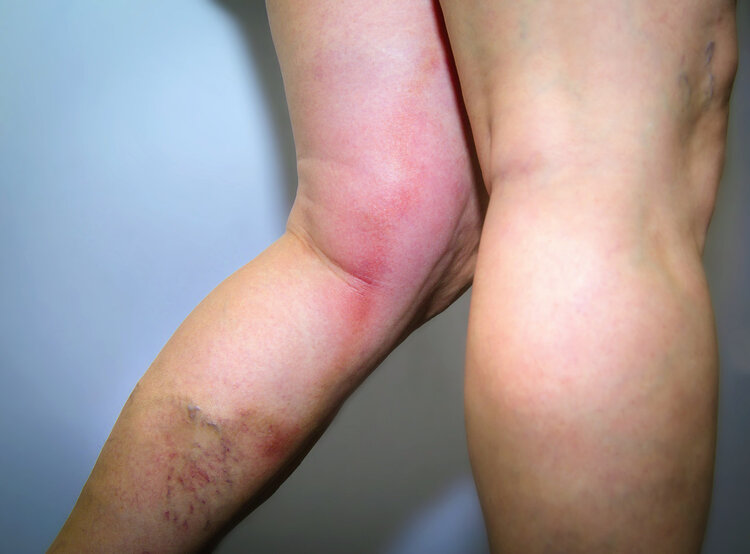

腿部肿胀: 当下肢发生血栓时,会导致下肢的血液循环受阻,继而引起大量的液体在腿部堆积,诱发腿部水肿,在休息后也无法缓解。